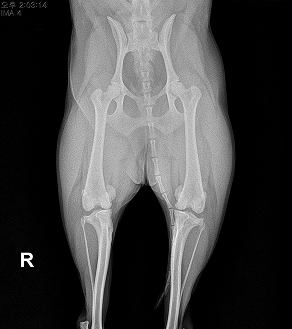

BEFORE

AFTER